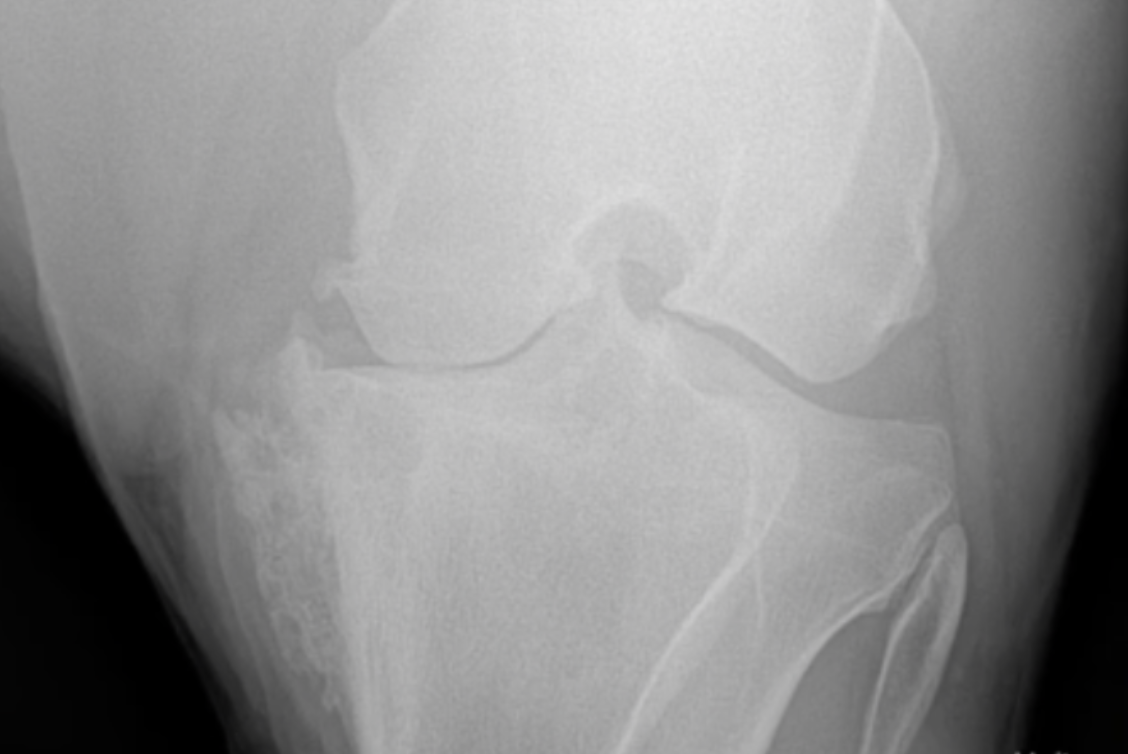

O diagnóstico precoce da osteoartrite é fundamental para iniciar o tratamento adequado e evitar danos adicionais às articulações. A Clínica de Equinos Prianti utiliza uma combinação de exames clínicos e de imagem, como radiografias e ultrassonografias, para identificar a presença da doença e determinar a extensão do problema.

Após o tratamento da osteoartrite, é fundamental cuidar adequadamente dos cavalos para evitar recidivas e garantir seu bem-estar a longo prazo. Recomendamos realizar exames regulares, como radiografias e ultrassonografias, para monitorar a evolução das articulações. Além disso, é essencial manter uma dieta balanceada e fornecer suplementos nutricionais específicos para promover a saúde das articulações.